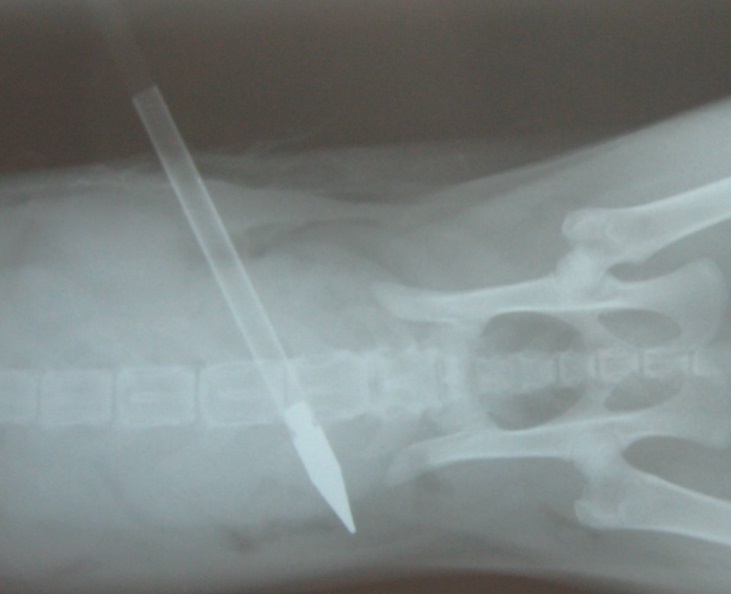

- 編號: 1823

主題: 高雄市蓄意射殺流浪貓 申請者姓名: 莊先生 花色: 申請日期: 2013-01-17 11:49:22 申請者部落格: 申請者臉書網址: 所在縣市/合作醫院: 高雄市/新德民動物醫院 治療費用: 18050元 需求人數: 20人 已結案 (2013-08-06 13:55:18) 報名人員: Slowsnow Hsu(已付款)、德千容茉、馬豆漿(已付款)、桂芳手藝行(已付款)、EAnson Chen(已付款)、心慈劉(已付款)、田小甜(已付款)、PS Yeh(已付款)、PS Yeh(已付款)、PS Yeh、PS Yeh(已付款)、Bubu Wang(已付款)、盧雨青(已付款)、Kit Mimicat(已付款)、Rebecca Chen(已付款)、Volu Chen(已付款)、heyblack(已付款)、游淑玲(已付款)、Miaow(已付款)、吳小菲(已付款)、lavinia x2(已付款)、 候補人員: Yuan-Hsin Kuo、KO.PON、盧雨青、 動物病情說明: 高雄市流浪貓被人惡意拿三角弓箭射殺!

被人蓄意射殺的虎斑貓

已經完成緊急手術

手術很成功.已經把鐵箭取出 不過72小時內都算危險期